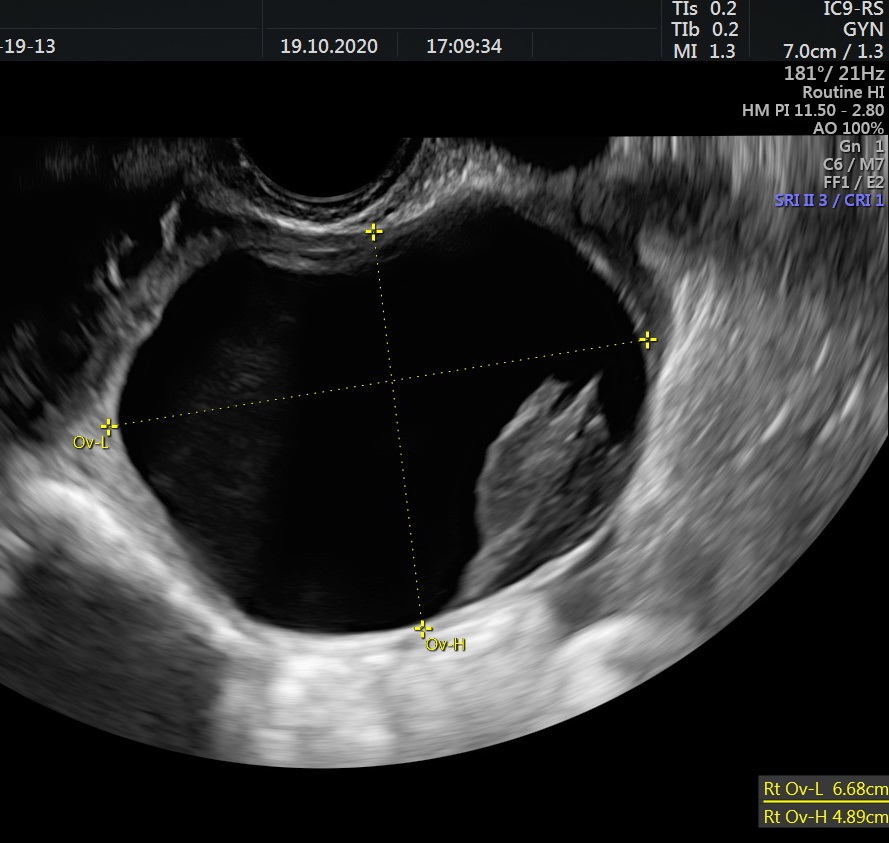

November 3, 2020- Fig 01 – transvaginal ultrasound

Case courtesy of Dana Nedelcu MD